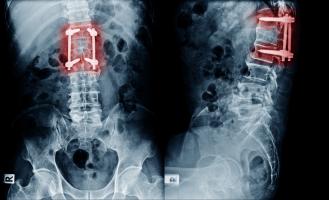

Actualité publiée il y a 3 semaines 3 joursFUSION VERTÉBRALE : Vers de nouveaux implants intelligents